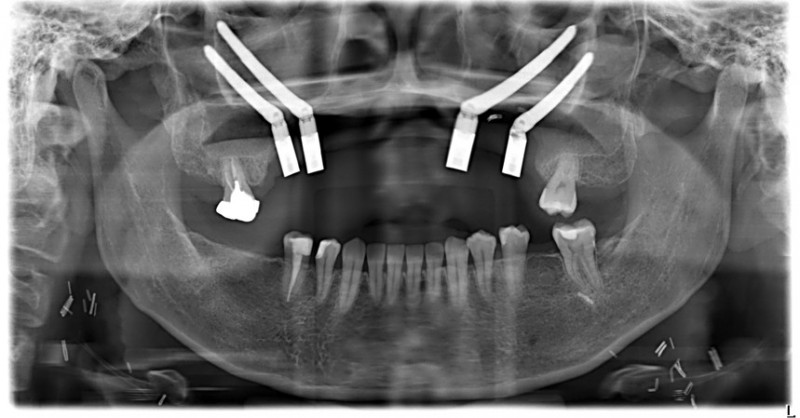

〔記者蔡淑媛/台中報導〕40歲許小姐罹患上顎牙齦癌,需手術切除大範圍上顎骨,不僅影響外觀,口內鄰近腫瘤的10顆牙齒亦需一併切除,透過電腦數位模擬技術及導航系統輔助,一日精準完成上顎口腔癌腫瘤切除、頸部淋巴清除、顴骨植牙及游離皮瓣重建,現在已成功恢復正常咀嚼功能,生活品質大幅提升。

中山附醫口腔顎面外科由醫師邱昱瑋、陳怡孜及陳珮吟組成醫療團隊,採用電腦數位模擬手術,術前先模擬腫瘤切除範圍,再模擬出切除後牙齒應有的排列位置,若上顎骨先前已被部分切除,透過電腦模擬將植體植入顴骨當中。

許小姐進行手術時結合切割導版與電腦導航系統輔助,醫師將所有相關手術程序於同一日一次完成,上顎口腔癌腫瘤切除、頸部淋巴清除、顴骨植牙及游離皮瓣重建,都精準完成,大幅縮短治療時程,降低患者身體負擔,生活品質大幅提升。